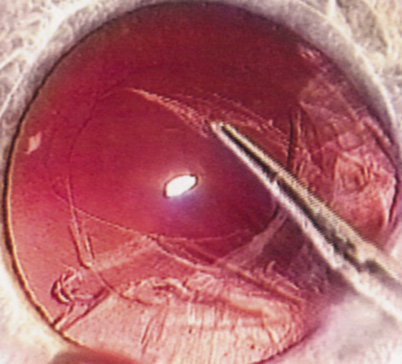

HYDRODISSECTION Hydrodissection can be performed after the surgeon has successfully completed capsulorrhexis.97 If the capsulorrhexis is not intact, fluid forced around the interior of the capsule may cause the bag to splay open. With capsulorrhexis, hydrodissection is a safe and extremely useful maneuver. Hydrodissection can be thought of as two maneuvers: hydrodelineation and cortical cleaving hydrodissection. By placing a 27-gauge cannula on a syringe filled with balanced saline solution (BSS), the surgeon can direct fluid beneath the residual anterior capsular rim to create a cleavage plane. Depending on the direction the fluid wave takes, different lamellae of the cataract will be separated. Hydrodelineation is the term used when the cleavage plane separates the adult nucleus from the fetal nucleus or the adult nucleus from the more peripheral epinucleus. Hydrodelineation often results in the characteristic golden ring sign (Fig. 11). Cortical cleavage occurs when the cortex is separated from the capsular bag (Fig. 12). Finding the cortical cleavage plane may be facilitated by gently lifting the capsular margin away from the cortex with the BSS cannula before injecting. Several small bursts of fluid allow the surgeon to monitor progress of the fluid wave. When dealing with a soft nucleus, the authors strive to perform true cortical cleaving hydrodissection. For a hard nucleus, hydrodelineation allows manipulation of less of the nuclear bulk, although the remaining epinuclear shell must be addressed in an additional step. Hydrodelineation is particularly useful if the nucleus is not freely mobile after cortical cleaving hydrodissection.